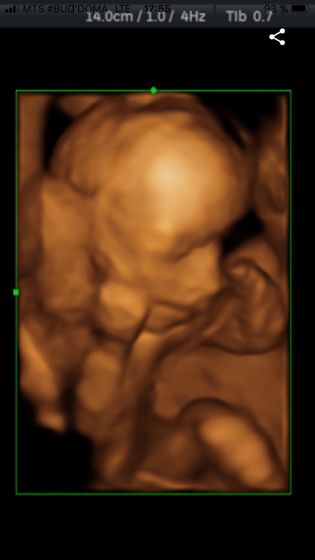

Привет всем). Живот уже очень заметен. Пупочек не вылез, но чувствую вот вот и он выпрыгнет) малыш постоянно выдавливает на пупок. Шевеления чувствую хорошо. Последние 2 дня ребёночек вообще не угомонный) танцует по всему животу) раньше чувствовала шевеления в основном когда лежала или сидела, а сейчас стою или иду, без разницы, чувствую и вижу как он там бьется) иногда вылазит в одно место и получается вот такой ширик, по ощущением это головкой он вылез) в основном по утрам так вылазит) вот мой животик) с первого скрининга нам говорят что мальчик) фото малыша на 19 неделе второе фото, на 21 неделе первое фото. Молозиво течёт сильно, ношу подкладки под грудь. Ходила на узи из-за непонятных схваток. Но уже поняла что это тренировочные. Знаю что тренировочные, так как врач сказал, не сама придумала)первая беременность, по этому не знаю ничего, и из-за этого постоянно переживаю. Вес у нас на 21 неделе 405 грамм) по показателям все в норме) делитесь своими ощущениями, фотографиями)